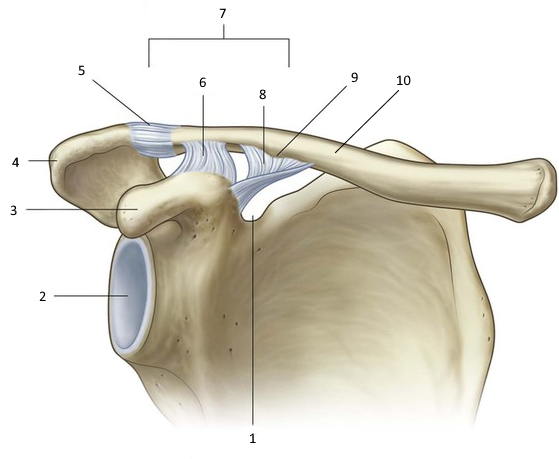

РОЗПІЗНАЙТЕ ДОДАТКОВІ ЕЛЕМЕНТИ ЦЬОГО СПОЛУЧЕННЯ.

варіанти відповідей

ЗВ'ЯЗКИ